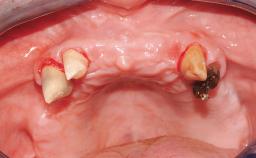

An 83-year-old male patient requested treatment for his existing maxillary complete overdenture and mandibular complete denture. He reported no general medical conditions of significance that would affect his dental treatment and was taking no prescription medication. He denied suffering from oral pain and displayed no evidence of parafunctional habits or temporomandibular joint disorder. Oral and radiographic evaluation revealed two retained maxillary teeth (13 and 15) supporting prefabricated ballshaped attachments. Both teeth were mobile and associated with active periodontal disease and extensive dental caries; these were considered non-restorable and were recommended for extraction. The patient’s existing complete maxillary and mandibular prostheses were approximately 2 years old. He was very satisfied with the appearance of both prostheses. His chief complaint was related to the instability and lack of retention associated with the existing mandibular prosthesis.